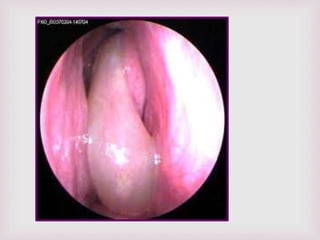

EXPLORACIÓN FÍSICA.

 Tumores con aspectos de uva.

 Se pueden encontrar en ambas fosas

nasales.

 Pueden adoptar la forma de la región

anatómica donde se encuentran.

 Blandos, tersos, translucidos.

 Ulceraciones con sangrado en ocasiones.

 Se encuentran en la parte superior de la

cavidad nasal y proceden del complejo

osteomeatal.

 La rinoscopia anterior

confirmara la presencia

de pólipos.

 Características macroscópicas de

los pólipos nasales…